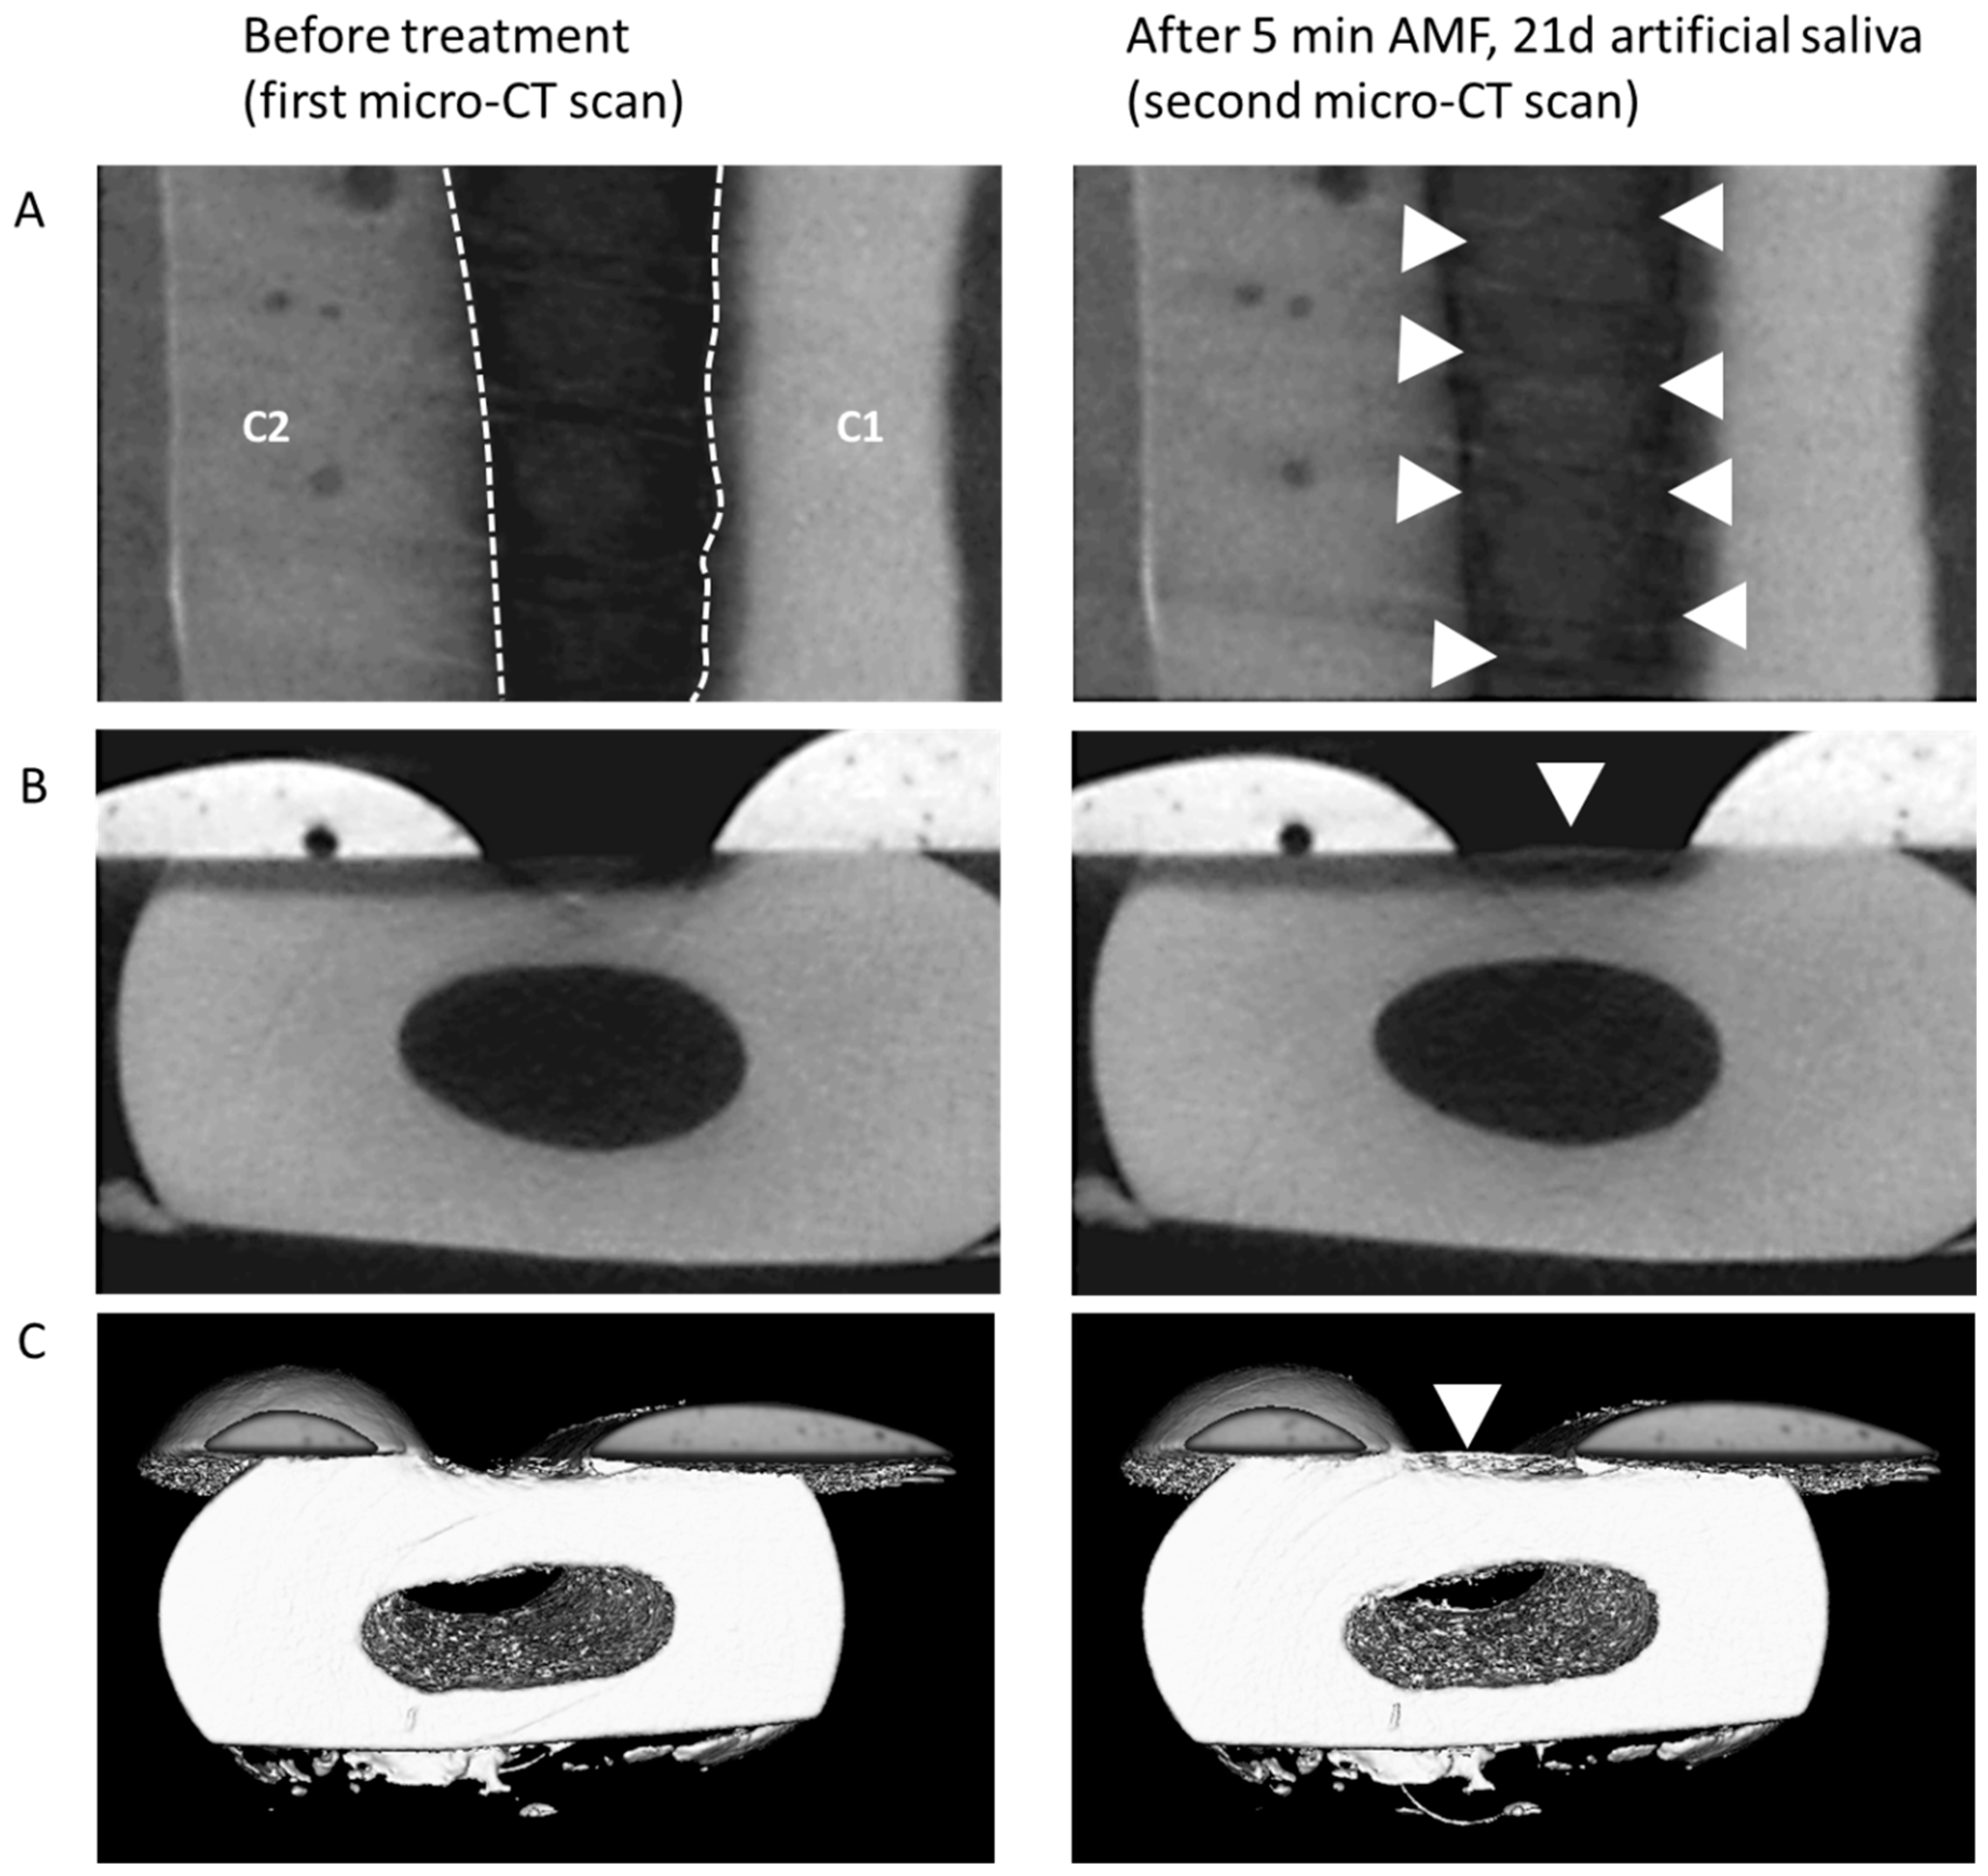

Figure 3. (A) Example of mineralization differences in a sample before treatment and following the 5 min treatment (shown: AMF) and incubation in artificial saliva for 21 days. Top view of gray scale images; C1/C2: protective composite material (see caption of Figure 4); hatched borders indicate the area of the defect, appearing relatively dark due to the absence of minerals. After treatment (right panel), an increase in mineralization was observed (arrow heads). (B) Side view of the same sample. (C) 3D-reconstruction of registered and segmented datasets of the same sample, with the increase in mineral located within the defect (arrowhead).